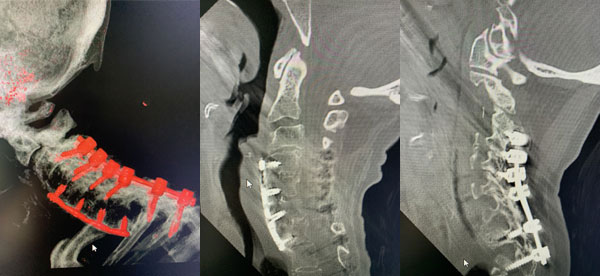

An MRI (Fig. 1) demonstrated severe stenosis at C2-3 with cord compression secondary to significant thickened posterior ligament and facet arthropathy. The patient had a posterior cervical laminectomy C1-3 to decompress the spinal cord and instrumented fusion C2-4.On exploration, the patient was deemed to be fused and the previous hardware was removed except for the lateral mass screws at C3 and C4 were left in. Postoperatively the patient had an uneventful course with some improvement in finger extensor strength.

Figure 3: Postoperative lateral c-spine x-ray showing removal of prior long posterior construct with final short segment fusion C2-C4. Note addition of bilateral C2 pars screws.